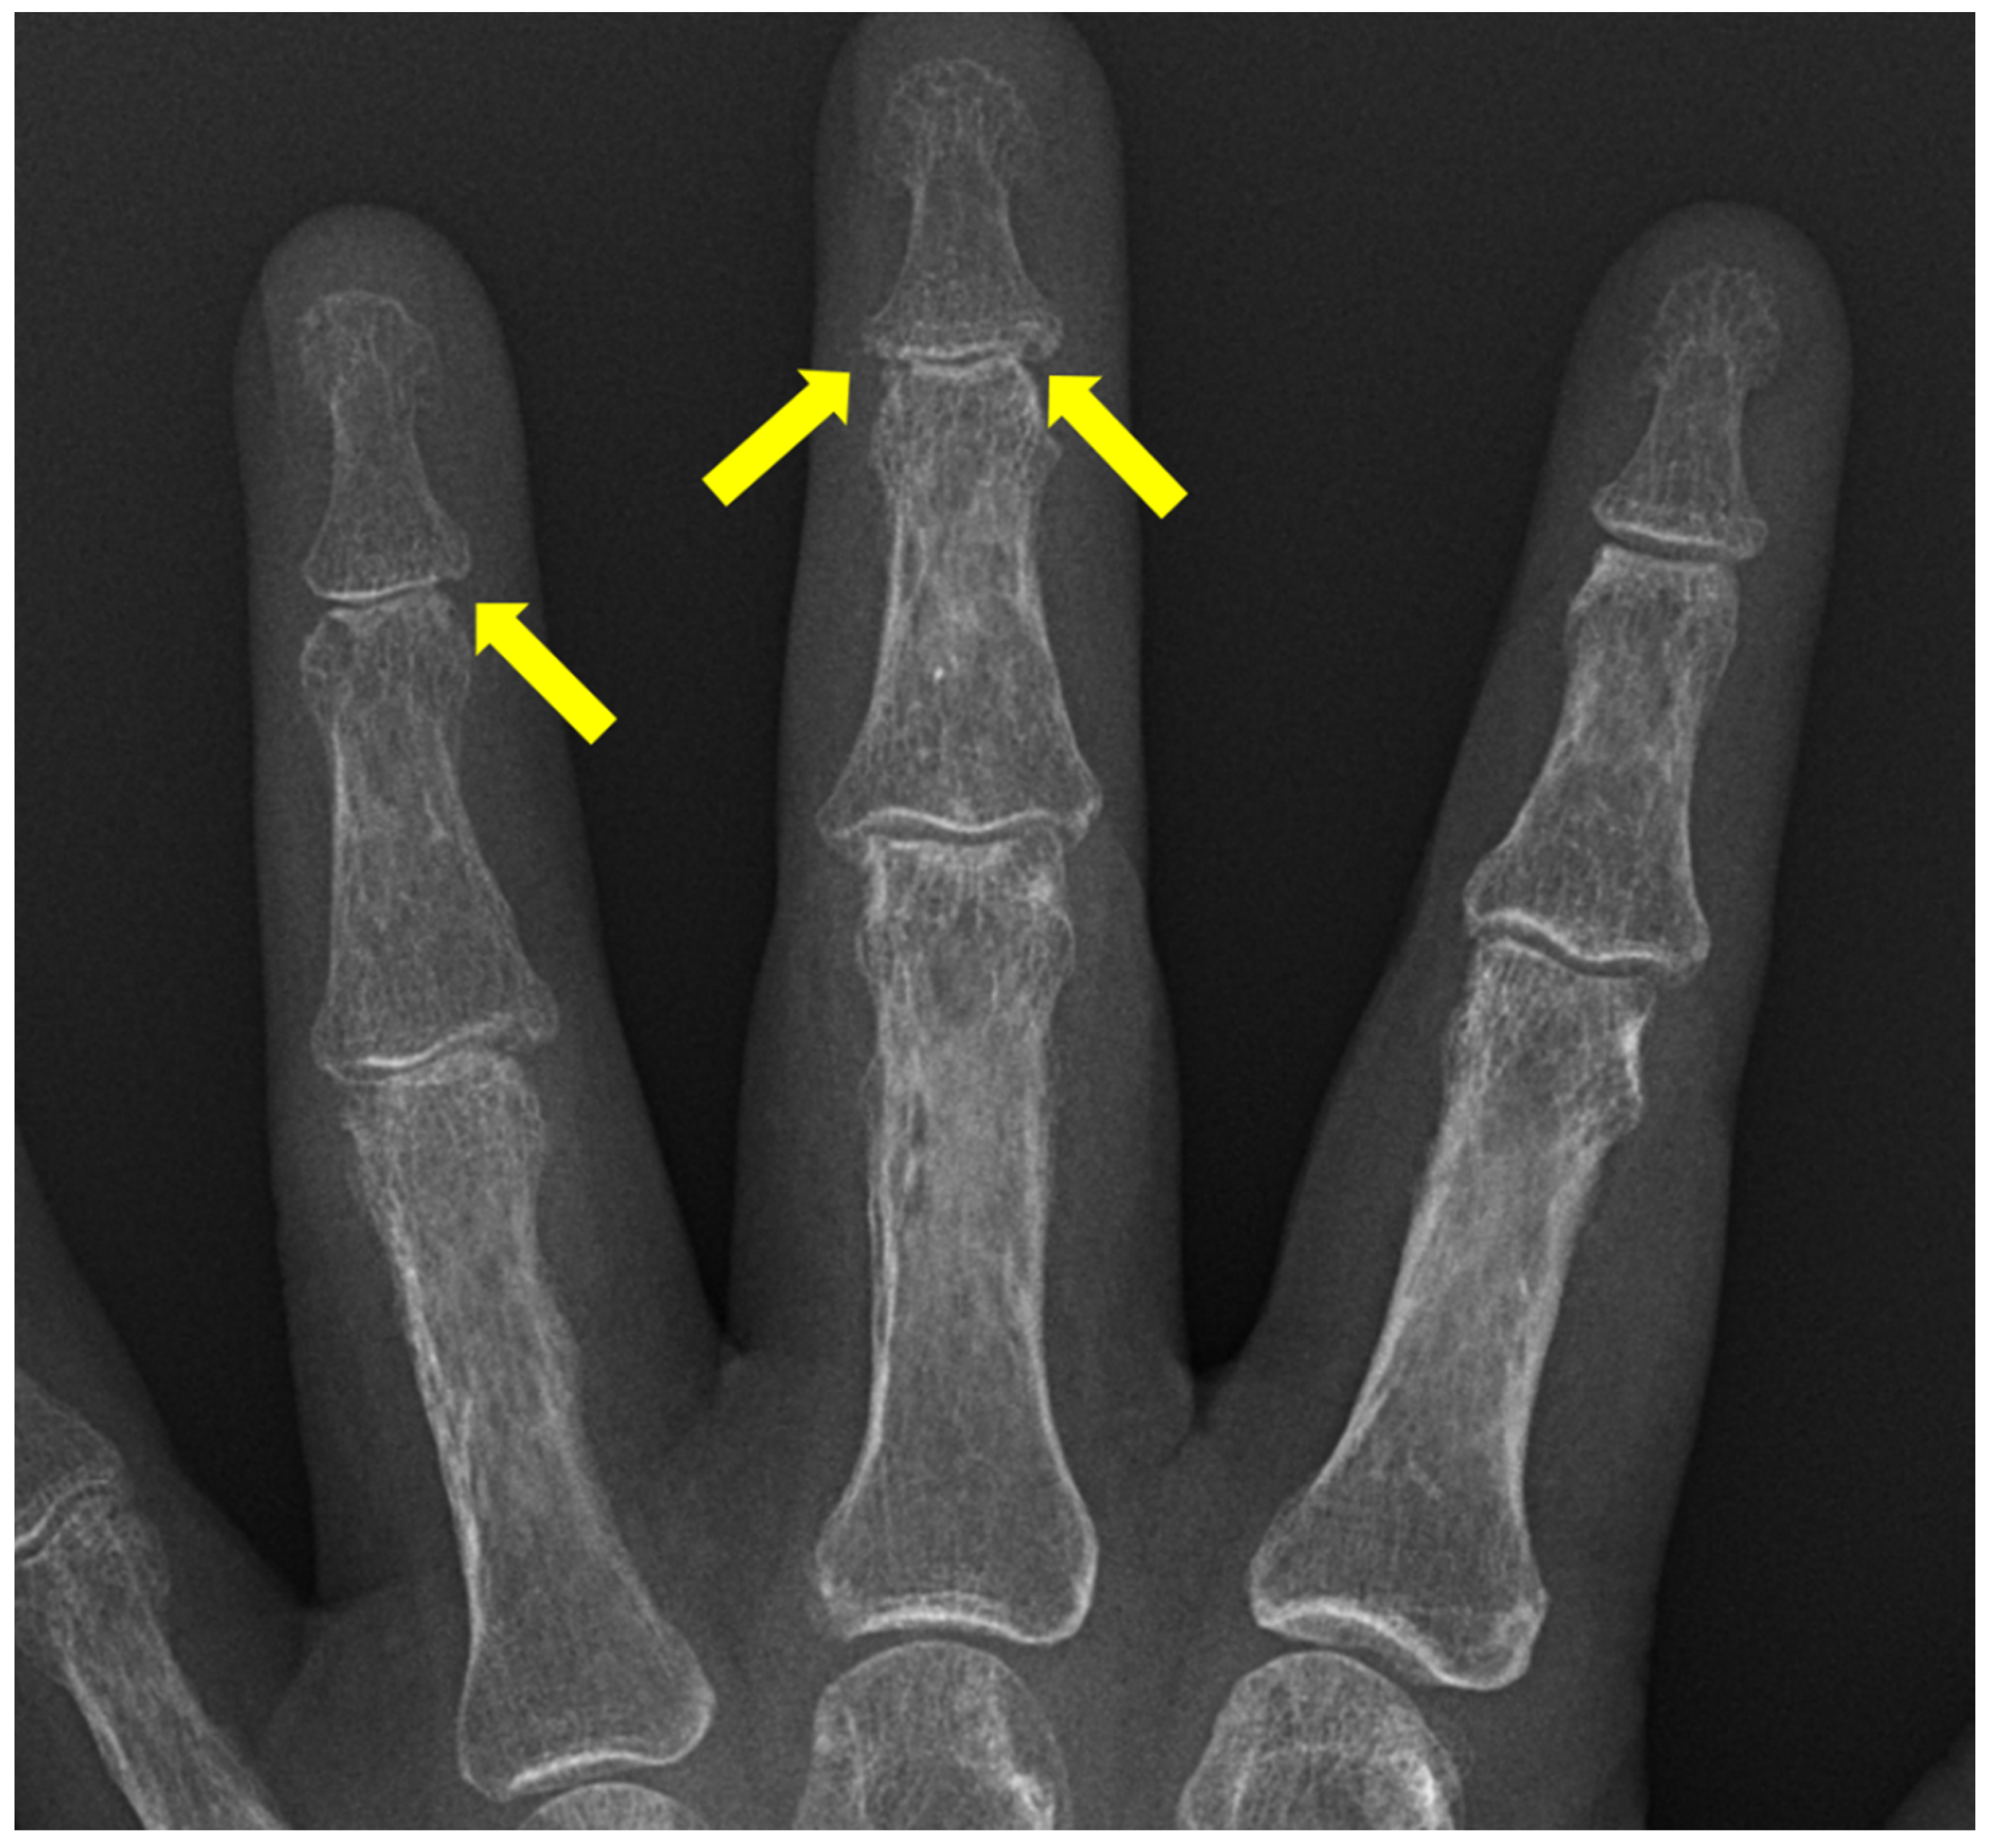

5. Psoriatic Arthritis (PsA)